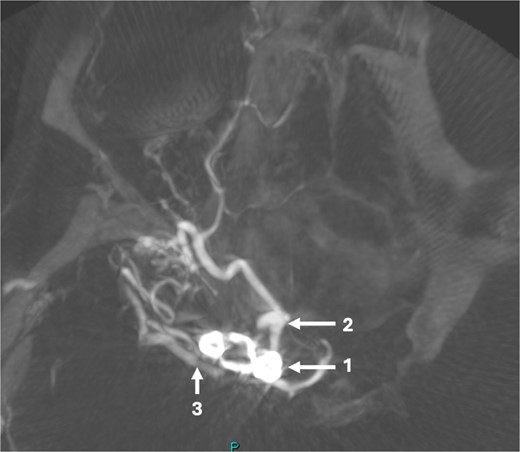

The DSA showed significant narrowing of the ACA and complete occlusion of the MCA distal to the clipped and fully occluded aneurysm. The right recurrent artery of Heubner, arising from A1, was hypertrophied and supplying the medial lenticulostriate territory. There was diffuse small vessel formation in this same area (Fig. 3). This DSA suggested the progressive distal stenosis secondary to the surgical clip led to anastomotic collateral formation, consistent with a radiological and clinical Moyamoya phenomenon. Patient’s symptoms were managed conservatively. Subsequent CT angiogram in 2018, 2021, and 2023 showed no further progression of the Moyamoya phenomenon.

Sagittal DSA demonstrating (1) Clip is in position across the terminal carotid. The frontal branch of the right MCA is supplied by collaterals from the (2) right ophthalmic artery (hypertrophied recurrent meningeal artery), right middle meningeal artery and right superficial temporal artery (via craniotomy site as pial synangiogenesis). There is collateral vessel formation consistent with Moyamoya phenomenon (4). (3) ICA. The A1 is not opacified likely due to the anterior communicating (ACOM) collateralisation.